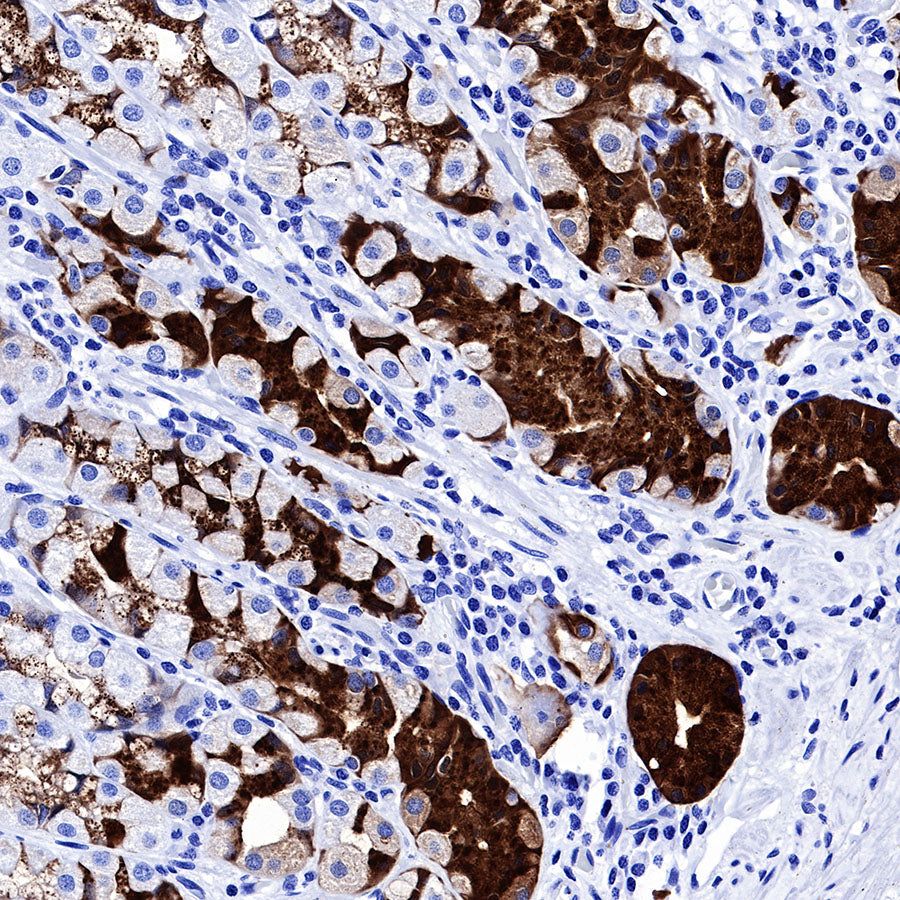

IHC shows positive staining in paraffin-embedded mouse stomach. Anti-PG II/PGC antibody was used at 1/1000 dilution, followed by a HRP Polymer for Mouse & Rabbit IgG (ready to use). Counterstained with hematoxylin. Heat mediated antigen retrieval with Tris/EDTA buffer pH9.0 was performed before commencing with IHC staining protocol.